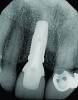

An osteotomy that used the dense cortical bone on the palatal aspect of the extraction socket was prepared, and a guide pin was inserted (Figure 5) to verify that the angulation was ideal. The implant was then inserted (Figure 6). Figure 7 shows the occlusal view of the implant in position. Note the gap between the palatally oriented implant and the buccal plate of the extraction socket.

Fig 6. Implant insertion.

Figure 6

Fig 7. Occlusal view of the implant after insertion.

Figure 7